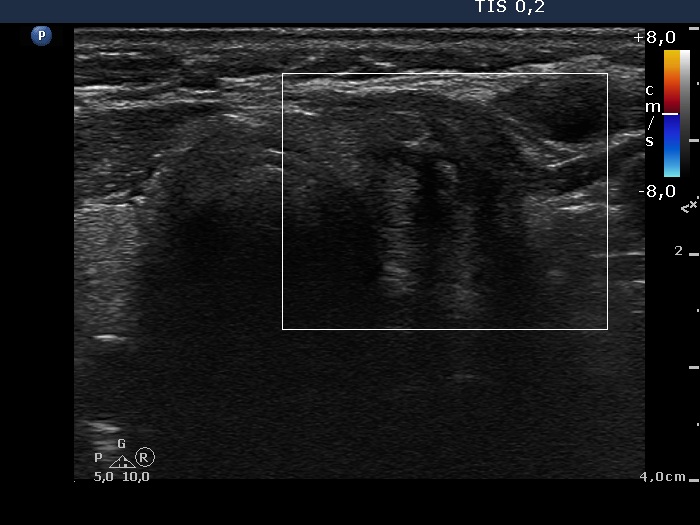

Ultrasonography. The right lobe was echonormal and contained several small, insignificant lesions. There was a hypoechogenic, irregularly shaped mass in the lower half of the left lobe. The lesion had a rigged, echonormal core which showed bright hyperechogenic granules. There were multiple incomplete acoustic shadows dorsal to the lesion which was avascular.